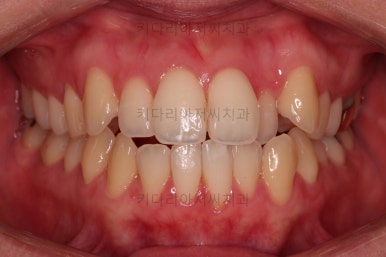

초진 시, 입안의 모습입니다.

좌측 송곳니가 덧니처럼 튀어나가 있고, 송곳니 옆의 작은 억므니가 안으로 쏙 들어가서 덧니 느낌이 더 강조되어 보이네요.

위아래 앞니가 긴밀하게 겹침이 없는 약간의 개방교합(오픈바이트, Openbite) 경향이 보입니다.

웃거나 말할 때 드러나는 치열이 삐뚤어서 심미적으로 좋지 못하고요.